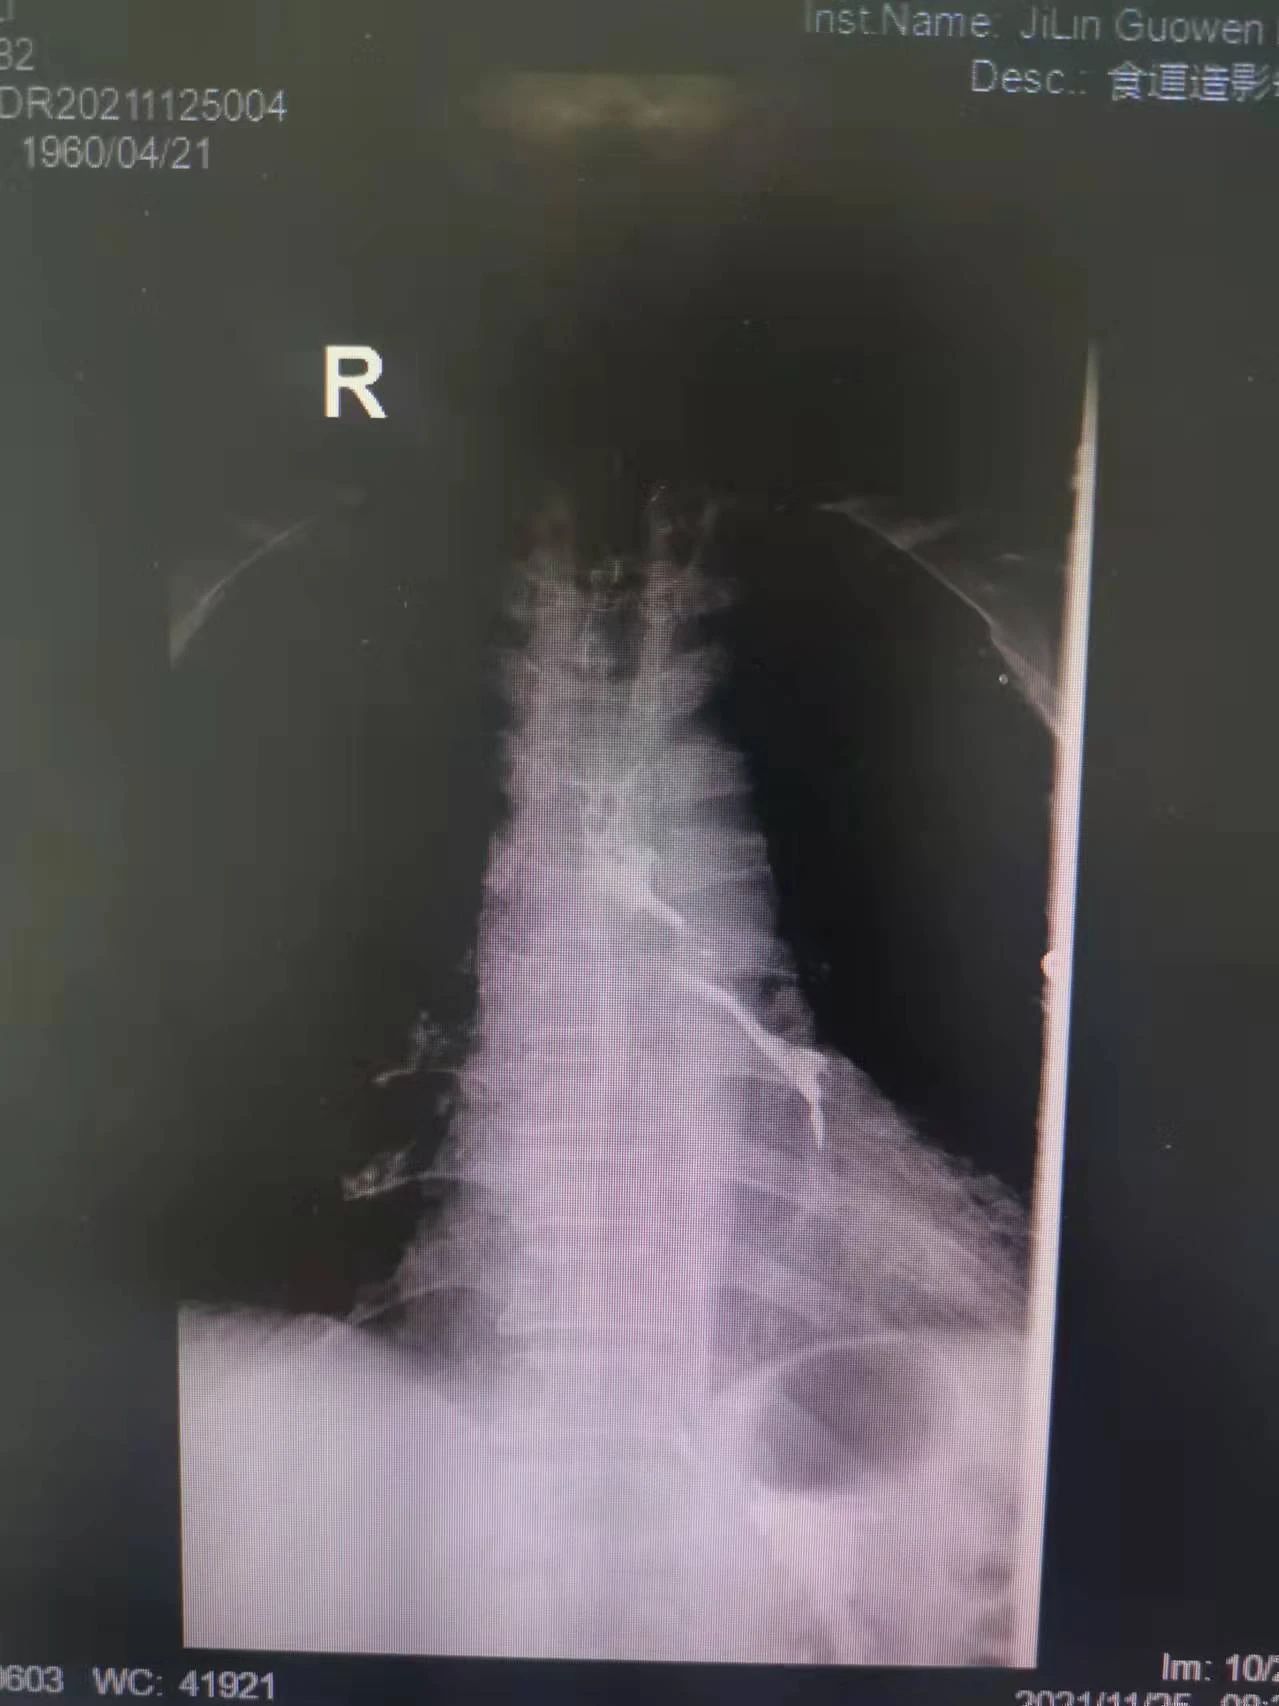

“大夫,我能喝點(diǎn)水么,我嗓子熱”今年61歲的付大爺患有食管惡性腫瘤。起初付大爺進(jìn)食時吞咽困難,每日進(jìn)食量極少,后隨著疾病的發(fā)展,付大爺進(jìn)食后伴隨劇烈嗆咳,經(jīng)系統(tǒng)檢查后,明確診斷為食管氣管瘺。為防止食物進(jìn)入氣管加重感染,付大爺聽從了醫(yī)生禁食水的意見。現(xiàn)如今,付大爺每日不光承受著癌癥所帶來的疼痛,還要承受著禁食水后仿佛置身于沙漠般的口干舌燥。這段時間里,喝一口水這么一個小小的愿望對于他來說都已成奢求!有著正常食欲卻無法進(jìn)食,可以想象對于人的生理及心理帶來多么大的創(chuàng)傷。家屬眼見付大爺痛苦不已,也是焦急萬分。

在這種情況下,我院介入二科侯主任決定通過介入治療中的食管支架植入來幫助患者實(shí)現(xiàn)這個愿望。手術(shù)當(dāng)日,侯主任在機(jī)器的幫助下,將一根細(xì)細(xì)的導(dǎo)絲穿過腫瘤到達(dá)付大爺胃部,然后再沿著導(dǎo)絲,把壓縮好的支架放在腫瘤里面。通過后撤導(dǎo)管,把壓縮的支架打開,支架把腫瘤撐開,讓食管不再堵塞。有了支架的支撐,付大爺就可以自由地吃東西了,哪怕食管和氣管有溝通,因?yàn)橹Ъ芨采w了腫瘤,通道堵住了,吃的東西也不會吸到肺內(nèi)造成感染。這時痛痛快快地吃上一頓,也不再是奢望!

手術(shù)很順利,付大爺也在術(shù)后第2天喝到了自己日思夜想的清水,露出了久違的笑容。從某種意義上講,介入食管支架置入術(shù)的成功實(shí)施,付大爺不能進(jìn)食的病已經(jīng)“治好”了,雖然從生理角度來說,付大爺可以通過終生使用腸內(nèi)營養(yǎng)來維持生存,但我們所做的是致力于給予患者更好的生存體驗(yàn),或者說是尊嚴(yán)。銘記并保持一名醫(yī)者的初心,我們要做的正如那句著名的墓志銘所說:有時去治愈,常常去幫助,總是去安慰。